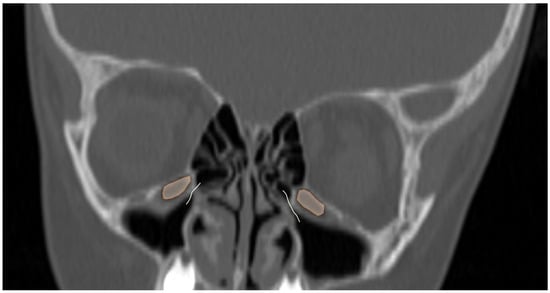

Figure 5.

Coronal reformatted CT image of a 6-year-old girl with bilateral Haller cells (orange areas) narrowing the osteomeatal complex (curved lines).

Additionally, the images were assessed for the presence of anatomic variants of the nasal cavity and PNS. Sinonasal variations were defined based on the European Position Paper on the Anatomical Terminology of the Internal Nose and Paranasal Sinuses [19]. According to this paper, the maxillary sinus is located between the orbital floor and alveolar process of the maxilla; the sphenoid sinus is the pneumatization of the sphenoid bone posterior to the rostrum; and the frontal sinus is defined as the pneumatization superior to a noticeable frontal beak [11,19]. The ANs are defined as the aeration of the protuberance on the lateral nasal wall, slightly anterior to the middle turbinate attachment (Figure 4). The Haller cell is an ethmoidal air cell, located below the orbital floor and lateral to a line parallel with the lamina papyracea (Figure 5). Onodi cell is the posteriorly located ethmoidal cell which develops just above and lateral to the sphenoid sinus (Figure 6). Concha bullosa is the pneumatization of the vertical segment of the middle turbinate (Figure 7) [19]. All anatomical variants were initially assessed by a single radiologist with four years of experience in maxillofacial CT imaging, who was blinded to patients’ demographic data, including age and sex. All assessments were done on a DICOM viewer (Medixant. RadiAnt DICOM Viewer [Software]. Version 2024.1. URL: https://www.radiantviewer.com (accessed on 1 November 2024)), after retrieval from the hospital PACS system to provide anonymized evaluation. The prevalence of each variant and the frequency of its bilaterality in each group were recorded. The evaluations were subsequently reviewed by a second radiologist with 11 years of experience. In cases of uncertainty regarding the presence of anatomical variations, a consensus decision was reached in consultation with a third radiologist with 13 years of experience.

Since Haller cells reach a stable prevalence after approximately three years of age, the comparison of maxillary sinus volumes was performed in patients older than three years. In this subgroup, the mean right maxillary sinus volume was 9.45 ± 3.93 cm3 in cases with Haller cells (n = 44) and 9.17 ± 4.37 cm3 in those without (n = 116; p = 0.704). On the left, the corresponding values were 9.28 ± 3.98 cm3 (n = 53) and 9.29 ± 4.68 cm3 (n = 107; p = 0.582).

Haller cells were more frequently identified after the first year of life, whereas Onodi cells tended to appear after the age of five, though their prevalence remained lower than that of other ethmoidal cell variants in older age groups. Similarly to sinus volumes, no significant difference in the prevalence of these anatomic variations was found between male and female patients. Awareness and preoperative identification of Haller and Onodi cells are crucial for surgical planning, as their presence may increase the risk of intraoperative complications [24]. Haller cells, located near the maxillary sinus ostium or the hiatus semilunaris, are associated with a higher risk of orbital injury during ethmoidectomy, while Onodi cells—also known as sphenoethmoidal cells—are situated close to the sphenoid sinus recess and have been linked to optic nerve or internal carotid artery injury during functional endoscopic sinus surgery (FESS) or transsphenoidal procedures [7,24]. Interestingly, the emergence of Onodi cells in parallel with sphenoid sinus pneumatization suggests that, although traditionally classified as posterior ethmoidal cells, they may in fact originate from the sphenoid sinus itself. Despite their anatomical proximity to the drainage pathways of the maxillary and sphenoid sinuses, respectively, our findings demonstrated that the presence of Haller cells did not significantly influence maxillary sinus volume, nor did Onodi cells affect sphenoid sinus volume in the pediatric population.